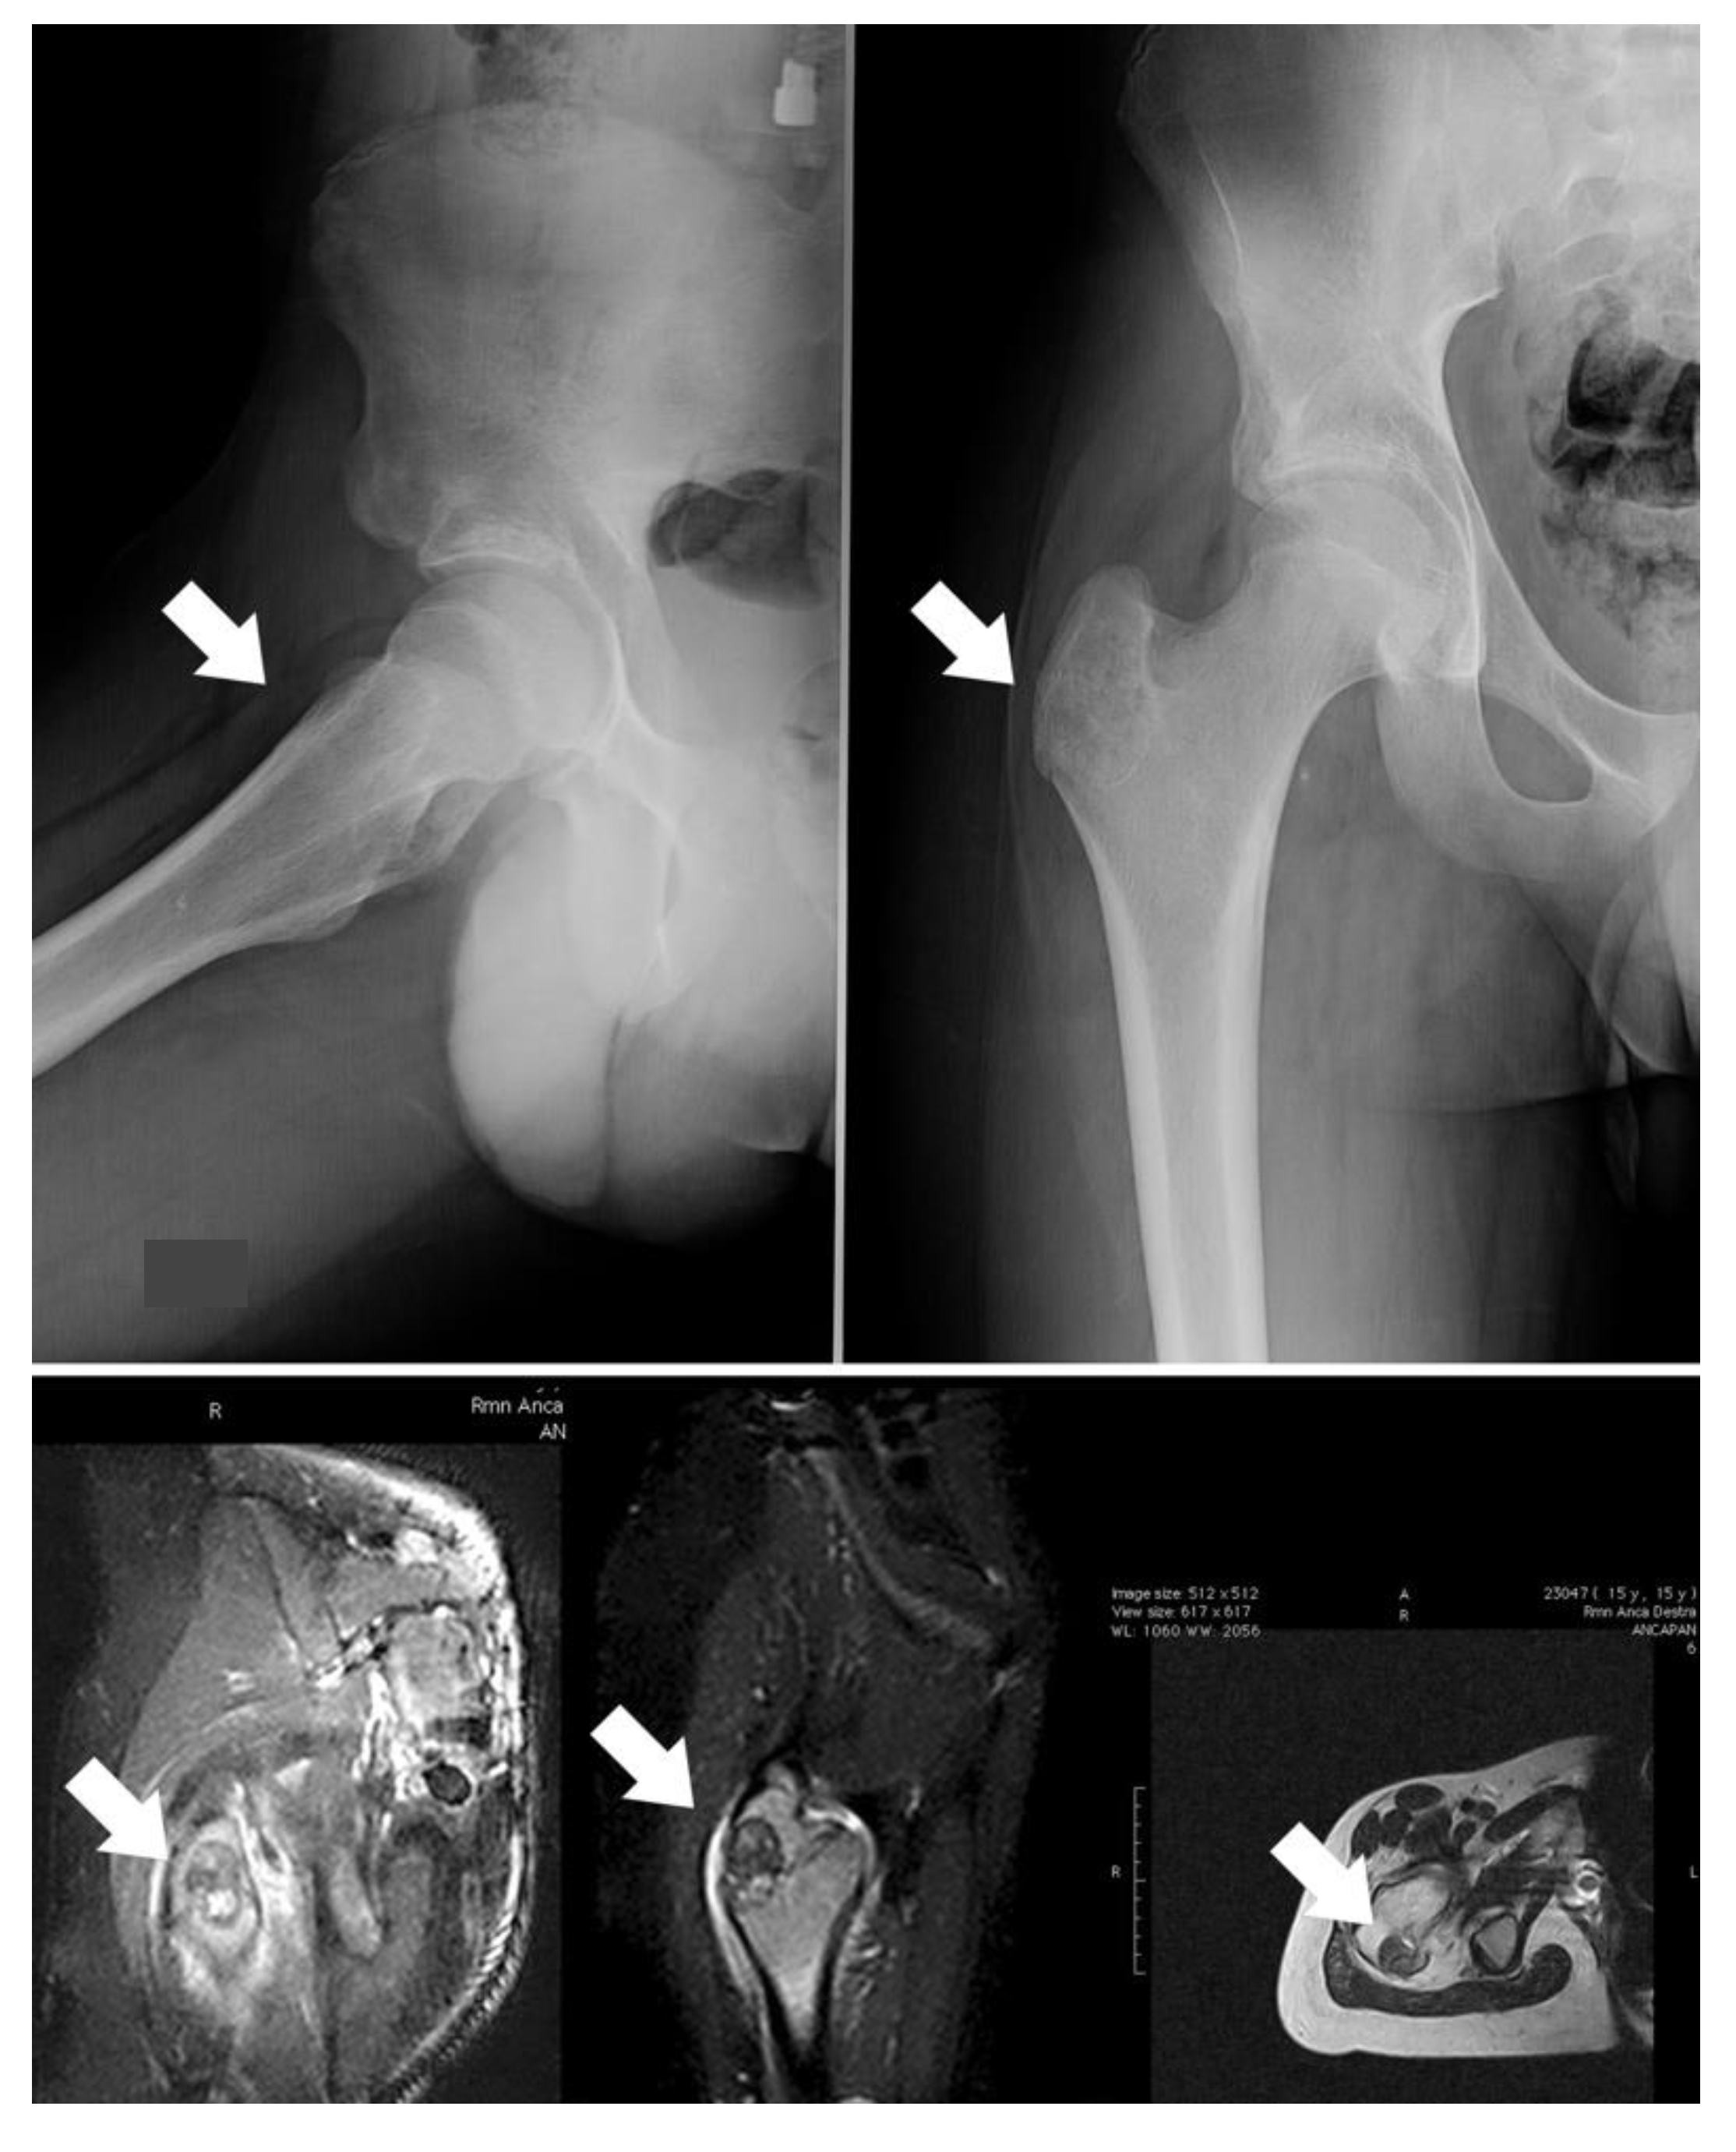

The gold-standard treatment for OBL is surgery; generally, intralesional surgery is suggested for grade 2 lesions (Figure 1A), whereas wide resection is more indicated for grade 3, more aggressive tumors or for lesions located in areas where a possible local recurrence could be difficult to treat (Figure 1B). Indeed, the site of onset also has to be assessed; a more aggressive lesion could be treated intralesionally if located in the distal femur, while lesions located in the spine or pelvis are more suitable for resection even if they do not have an aggressive appearance.

Figure 1. (A) Twenty-two-year-old male patient affected by stage 2 distal humerus OBL (white arrows): the lesion was considered suitable for intralesional surgery; (B) twenty-one-year-old male patient affected by a D3 left pedicle OBL (white arrows): wide resection was performed to decrease the risk of local recurrence.